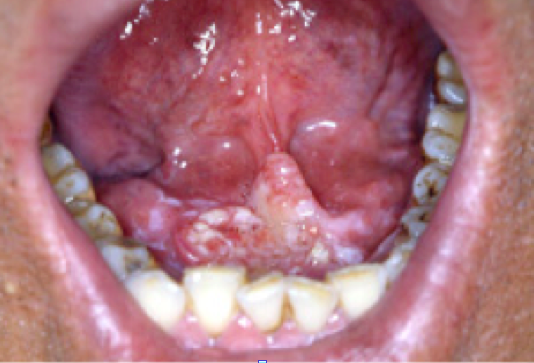

설암![]() |

치은암![]() |

구개암(입천정)![]() |

구강저암(혀아래)![]() |